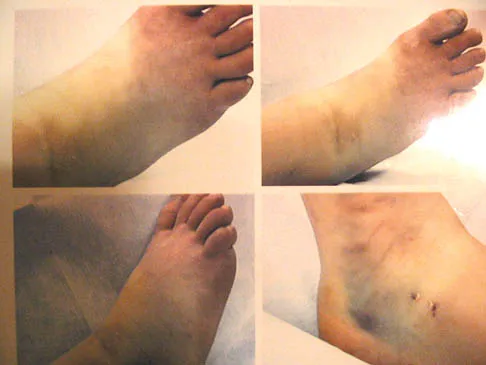

An 11-year-old girl sustained an injury to her right foot when a 500-lb headstone fell on it. The headstone was removed after 3 minutes. Radiographs show multiple midfoot fractures. Examination reveals severe pain that is worse with passive toe motion. Clinical photographs are shown in Figure 28. Management should consist of

Explanation